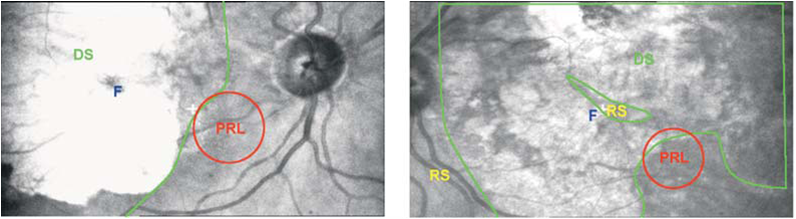

Se valoraron a 25 pacientes con miopía elevada. Se evaluó tanto la agudeza visual y la sensibilidad retiniana mediante microperimetría con el Scanning Laser Ophthalmoscope (SLO). Como resultado, 20 pacientes (80%) fueron rehabilitados por medio de ayudas ópticas monoculares, mientras que cinco pacientes (20%) fueron rehabilitados binocularmente. Se encontró una buena correlación entre la agudeza visual y la sensibilidad de la retina sólo cuando la patología macular no indujo grandes áreas de atrofia coriorretiniana, que es la que causa la falta de estabilización del Preferred Retinal Locus (PRL) o punto de mirada preferencial que se desarrolla en la visión excéntrica. De hecho, los mejores resultados en la lectura y la realización de tareas visuales diarias se obtuvieron mediante la estimulación de la visión residual en pacientes con sensibilidad de la retina mayor de 10 dB. Una zona bien circunscrita de escotoma absoluto con un nuevo locus definido de fijación retinana podría ser considerado como un factor predictivo positivo para el proceso de rehabilitación final.

Como conlusión, se requiere una evaluación más cuidadosa de la agudeza visual, sensibilidad de la retina y la zona de fijación preferencial (PRL) necesaria para prescribir las mejores ayudas ópticas para pacientes con Baja Visión, lo que reduce el impacto de la discapacidad en su vida diaria.